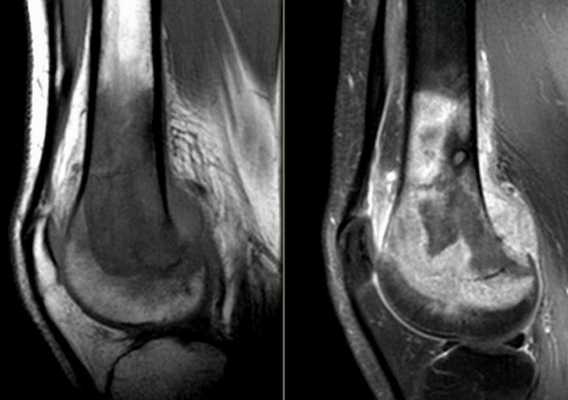

Компьютерная томография колена

КТ колена

С помощью компьютерной томографии визуализируют нарушения связочного аппарата, костных суставных поверхностей, гиалинового хряща, синовиальной оболочки и капсулы сочленения. Ограничение подвижности и боль возникают чаще при травмах, воспалительных и дегенеративных патологиях.

КТ коленного сустава позволяет диагностировать хондромаляции (разрушение хряща), повреждения менисков, разрывы крестообразных связок. В результате контрастной процедуры выявляют онкологические процессы, заболевания сосудов, липоартрит и пр.